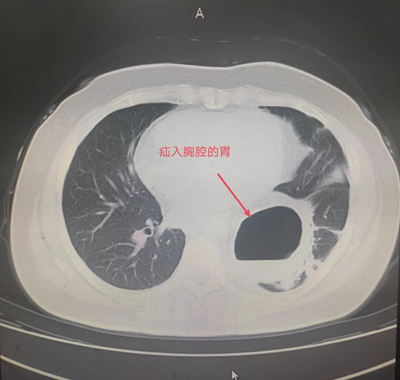

患者辛某,今年85岁,1年前患者因反酸、进食后反复呕吐于外院就诊。胸腹部CT检查提示:膈疝。胃十二指肠镜检查提示:食管外压性改变,膈疝,食管裂孔疝。患者长期营养不良,无法经口进食,只能通过鼻饲-空肠营养管置入进行营养,近日因营养管再次出现导管堵塞,随后被家人紧急送往日韩无码 住院治疗。住院后进一步检查诊断食管裂孔疝、肺部感染,既往患有脐疝、胸椎手术史,合并心律失常、低氧血症、代谢性酸中毒、肺大疱、心脏瓣膜疾病、左侧颈动脉斑块形成、腔隙性脑梗塞等老年病史。

由于患者年事已高,病情复杂,手术难度极高。普外科主任田德福充分考虑到患者年龄、病情实际,先组织科室任斌、尹超、杨洲明、何慢等专家进行危重症患者治疗方案讨论。随后联系医务科组织全院多学科MDT讨论,根据全院MDT多科室会诊结果制定了周密的手术计划,并针对高龄患者可能出现的并发症做好各类突发应急准备。在麻醉手术部、手术室的全力配合下,普外科专家团队在全麻腹腔镜下成功为老人实施了食管裂孔疝、膈疝、脐疝三疝同时手术,术中探及食管裂孔疝,直径约4cm,其旁左侧直径约7cm大小膈疝,食管裂孔疝内容物为小网膜组织,膈疝内容物为胃底、胃体大部及大网膜组织。脐疝直径约3cm大小。腹腔镜下进行食管裂孔疝、膈疝无张力修补及脐疝修补术。手术顺利,术中患者生命体征基本稳定。术后在全科医护人员的治疗和精心护理下,逐渐进行经口进流食、半流食。床上活动、渐下床活动。复查各项指标渐正常。胃肠功能恢复正常,于6月14日痊愈出院,近日回访患者一般情况良好。